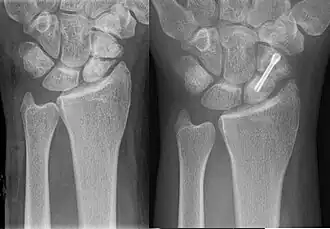

-

A subtle scaphoid fracture -

A more obvious scaphoid fracture on a scaphoid view X ray -

Radiolucency around a 12 days old scaphoid fracture that was initially barely visible.[13]